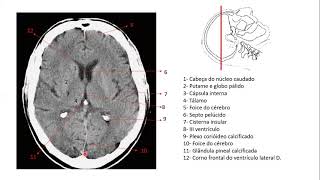

que o corpo caloso tem o joelho o corpo e o esplênio do corpo caloso nessa imagem em corte axial você consegue visualizar o joelho e o que seria o esplênio do corpo caloso Bom agora eu vou pegar uma imagem que dá pra gente visualizar bem os núcleos da base aqui pintado de verde a gente consegue visualizar o que seria o núcleo lente fore que é em formato de lente pode perceber que ele forma uma espécie de uma lente e ele é formado pela junção do putam e do Globo pálido lateral e o globo pálido Medial

aqui é bom dar um zoom deixar em tela cheia para visualizar mas dá pra gente ver a cápsula externa o que seria a cápsula externa né para visualizar melhor coloquei essa imagem que a gente tem do do do morfo funcional que dá para ver aqui ó o número sete seria a cápsula extrema o nove o claustrum e o oito a cápsula externa né então ali naquela naquela imagem anterior tá na verdade estão esses três juntos né aqui pintado de vermelho tô representando aqui pintado de vermelho eu tô representando a cápsula interna a cápsula interna também

é dividida em porções né de porção anterior o corpo e a porção posterior depois também vou fazer um vídeo colocando as principais funções dessas áreas que a gente tá falando aqui pintado de Laranja dá pra gente visualizar o núcleo calado que acompanha o ventrículo lateral em roxo a gente consegue visualizar o tálamo e agora um corte sagital pra gente visualizar algumas estruturas algumas repetidas e outras novas aqui como já tinha falado joelho corpo e esio do corpo caloso em verde o ventrículo lateral aqui em rosa representando O Aqueduto mesencefálico ou Aqueduto de silvios que vai